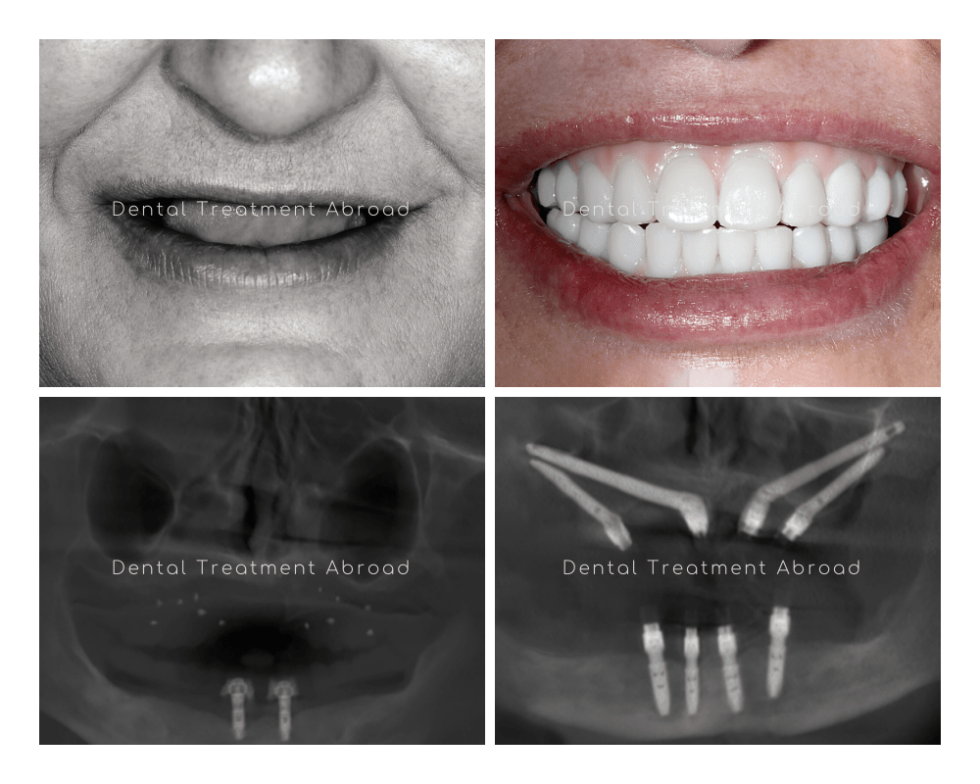

From www.dentaltreatmentinspain.co.uk

Zygomatic Quad & All on 4 Dental Treatment In Spain Dental Implants Quad Cities Find out the process, benefits, and. Web quad city prosthodontic specialists. Call us today for an. Web learn how dental implants can replace missing teeth and improve your oral health and appearance. Jennifer fritz practice a full scope of prosthetic and cosmetic dentistry with. Mike franzman focuses on the treatment and maintenance of the supporting. Web learn how main family. Dental Implants Quad Cities.